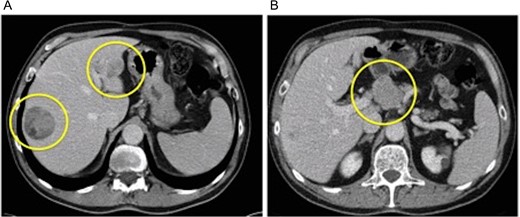

A 72-year-old man was known for a chronic HCV infection, treated with success in the past with actual undetectable viremy. On routine ultrasound screening, a hepatic nodular lesion was found in segment 8 (S8). Alpha-fetoprotein was low (4.7 ng/ml) and liver function was normal. A 4-phase CT-scan confirmed a 5.5 × 4.7 × 5.2 cm3 lesion typical for HCC, and showed a second 2 cm hypovascular lesion in segment 2 (S2) (Fig. 1). The staging was negative for distant metastases, but a 4.6 × 3.7 × 4 cm3 lymph node was observed in the coeliac region, retrospectively present on a CT-scan made 3 years before. The MRI confirmed the CT findings. A percutaneous US-guided biopsy of the S8 lesion confirmed a classical HCC, with a trabecular growth pattern, while a biopsy of the coeliac node, by US-endoscopy, showed carcinoma cells. After initial proposition of a palliative treatment with Sorafenib, the patient’s case was re-assessed, basing on the possibility of two different lesions: a classical hypervascular HCC in S8, and a hypovascular and slow growing second one in S2 with a positive lymph node. An F18-FDG PET scan showed a clear hypermetabolism in the S2 nodule and in the coeliac lymph node, while no capitation was found in S8 lesion.

(A) Venus phase of dynamic CT-scan showing two hepatic nodules (classical HCC in S8 and medullary-like HCC in S2) and (B) large lymph node in the coeliac region.